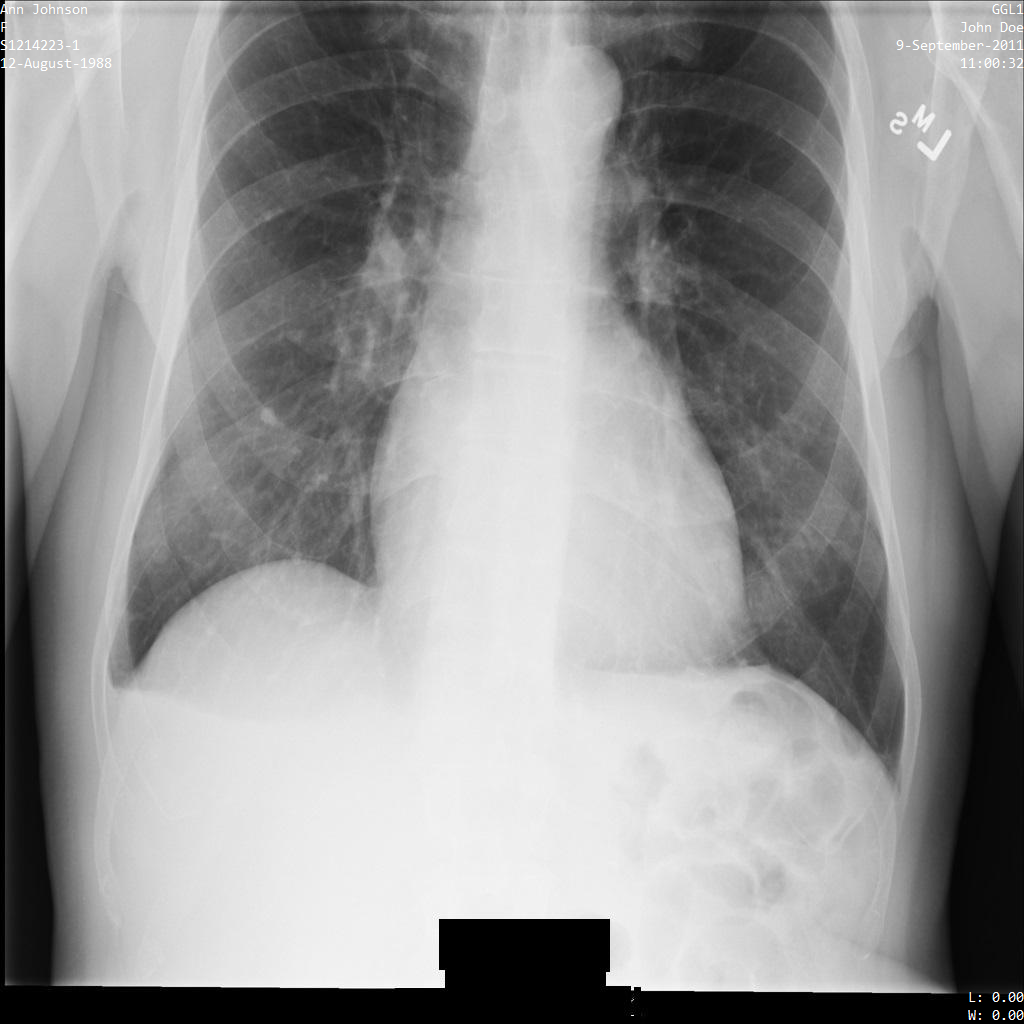

Después de enviar la imagen a la API de Cloud Healthcare mediante el perfil de filtro de etiqueta ATTRIBUTE_CONFIDENTIALITY_BASIC_PROFILE, la imagen aparece de la siguiente manera. Mientras se ocultan los metadatos que se muestran en las esquinas superiores de la imagen, permanece la PHI quemada que se encuentra en la parte inferior de la imagen.

Para quitar también el texto grabado, consulta Cómo ocultar el texto grabado de las imágenes.